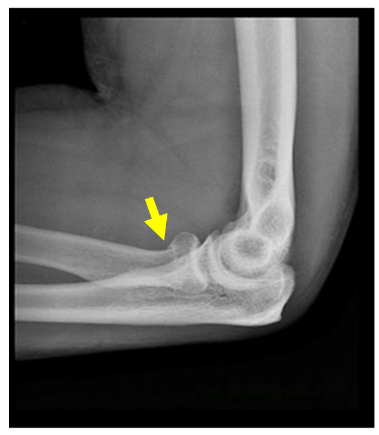

What is a radial head/neck fracture?

This is a fracture of one of the bones in your elbow.